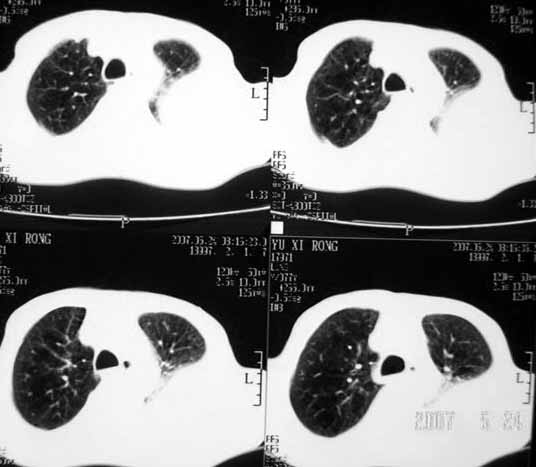

以下是引用luochengyi在2007-5-24 14:33:00的发言:[br]考虑左下肺癌。左侧胸腔积液。

以下是引用adams在2007-5-24 17:12:00的发言:[br]支持“考虑左下肺癌,左侧胸腔积液,建议胸水检查”。[br] [br]

以下是引用fumaogui在2007-5-24 16:20:00的发言:[br]左侧胸腔积液.[br]左下叶不张考虑中心型肺癌[br]建议纤支镜检查.